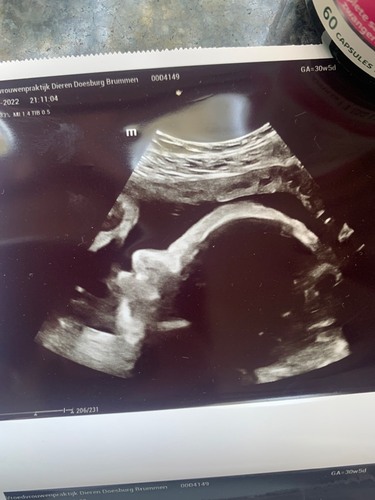

Ik vond de echo foto’s heel mooi om te zien maar die neus bleef maar terug komen, zo groot.. het leek wel een snavel 🤣 ik weet nog dat, toen ze net geboren was, dat ik zei; “oh maar, ze heeft helemaal geen grote neus, maar een heel lief kleintje”.

Nu 6,5 maanden later, na de geboorte: ik ben zo verliefd op haar! Vanaf het eerste moment dat ik haar zag en het is alleen nog maar meer en meer geworden❤️